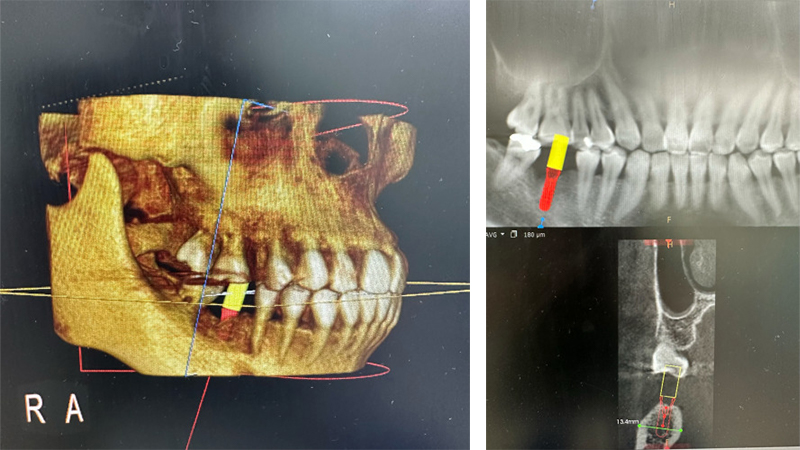

実際の治療例です。

左上5番目が欠損してるので、インプラントを埋入していきます。

インプラントを入れた状態の写真とレントゲンです。